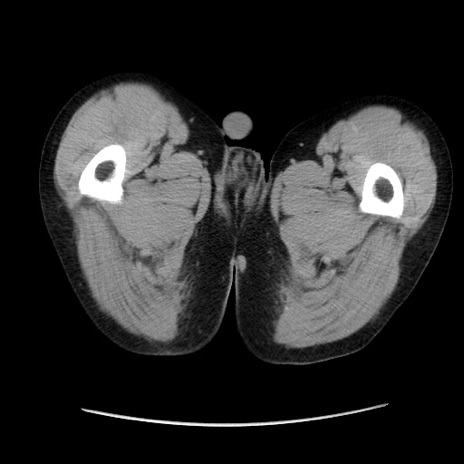

症例37(横断像)

【症例】40歳代 男性

【主訴】腹痛

【現病歴】4時間ほど前に電車に乗車中に臍部上より腹痛出現。徐々に増悪し起立困難となり、救急外来受診。生ものは数日食べていない。今朝お雑煮を食べた。

【身体所見】BT 36.8℃、BP 117/84mmHg、HR 91/min、SpO2 97%、苦悶様、腹部:臍上部広範囲圧痛あり、反跳痛±

【データ】WBC 8100、CRP 0.03